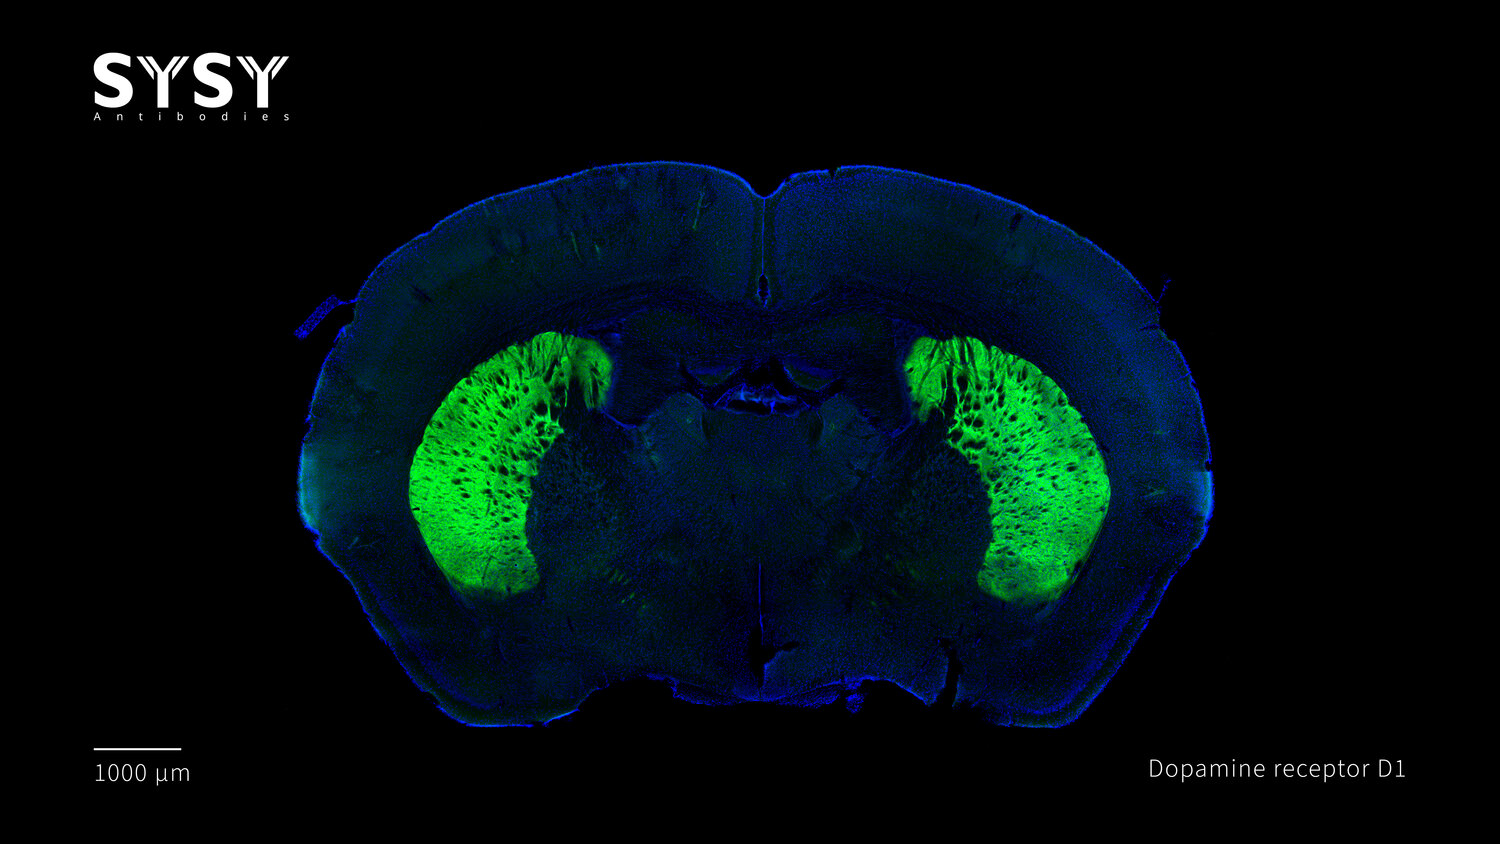

Dopamine receptor D1

Indirect immunostaining of a formaldehyde fixed coronal mouse brain section with rat anti-Dopamine receptor D1 antibody (cat. no. 376 017, dilution 1 : 500).